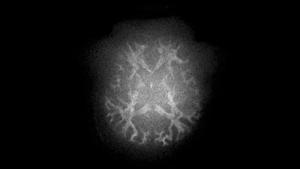

MAGNETOM Cima.Xによる拡散強調画像 |

同社従来機(MAGNETOM Prisma)による拡散強調画像 |